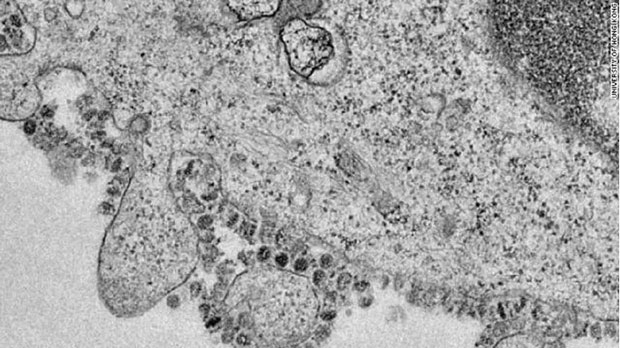

Kada je čovek pre 10-ak hiljada godina od lovca sakupljača postao poljoprivrednik stočar, bliski kontakt sa životinjama omogućio je razvoj brojnih bolesti koje su prelazile sa životinja na ljude i obratno – tzv. zoonoza. Zanimljivo je da se tada očekivano trajanje ljudskog života značajno skratilo. No, sigurnost dostupnosti hrane ipak je predstavljala evolutivnu prednost. Danas se smatra da je najskoriji zajednički predak svih korona virusa star najmanje 10.000 godina. Procenjuje se da se SARS, koji je zoonoza, odvojio 1986. Smatra se da je sa slepog miša prešao na vrstu divljih mačaka - cibetke, a potom na tržnicama na ljude. Novi korona virus 2019 n-CoV (stvarna snimka dole) prvi je put zabeležen krajem 2019. godine, genetski se podudara sa SARS-om više od 70%, a klasifikovan je kao vrsta betakorona virusa. Takođe se smatra da je potekao od šišmiša, no posrednik za sada nije poznat.

.jpg)